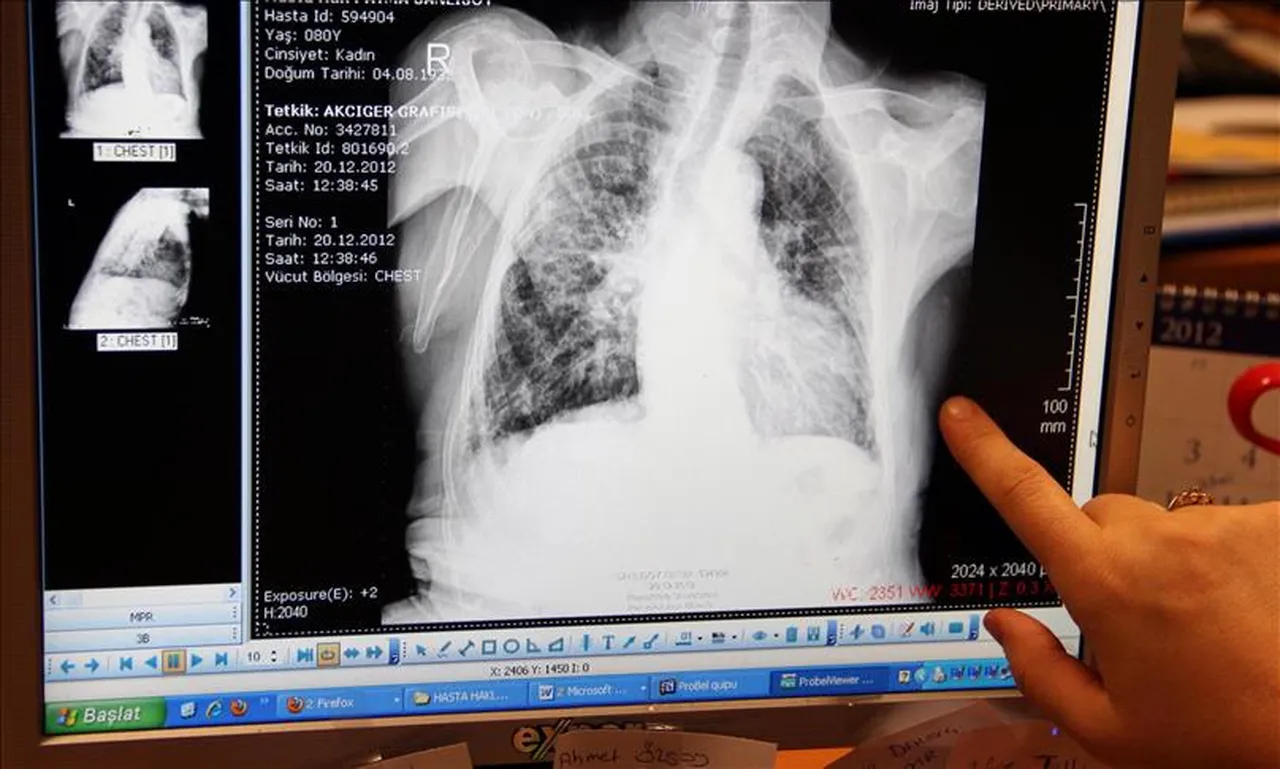

“İki haftadan uzun süren öksürük, balgam, bazen kanlı balgam, göğüs ağrısı, gece terlemesi, kilo kaybı, ateş ve halsizlik, tüberküloz belirtisi olabilir” diyerek uyaran Dr. Aktaş, “Tüberkülozun teşhisi; balgam incelemesi, akciğer grafisi ve gerekli laboratuvar testleriyle konulabiliyor. Tedavisi ise düzenli ve kesintisiz kullanılan ilaçlarla, genellikle 6 ay süren etkili bir süreçtir. Tedavinin yarım bırakılması hem hastanın iyileşmesini geciktirir hem de ilaç dirençli tüberküloz riskini artırır” dedi.

NASIL TANI KONULUR?

Tüberkülozun kesin tanısı bakteriyolojiktir. Tüberkülozdan şüphelenilen hastalardan usulüne uygun üç balgam örneği alınır. Balgam çıkaramayan hastalarda balgam indüksiyonu ya da açlık mide suyu incelenir. Bu yolla da örnek alınamazsa bronkoskopik lavaj sıvısı bu amaçla kullanılabilir.